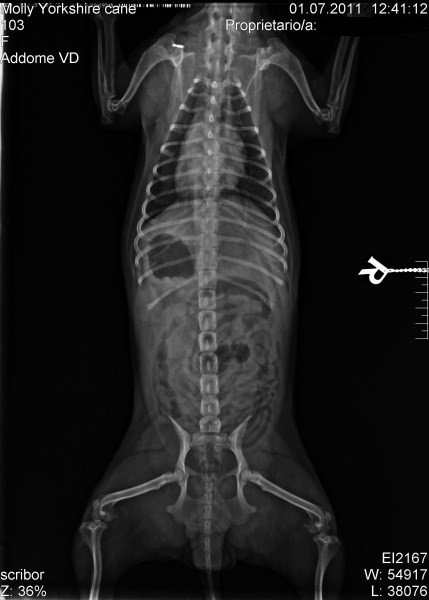

Radiografia

L’esame radiografico è uno step fondamentale nell’indagine diagnostica di base. La clinica è dotata di un apparecchio radiografico digitale diretto ad alta risoluzione che consente di ottenere immagini dettagliate e visualizzate istantaneamente, riducendo così il tempo di esecuzione dell’esame e risparmiando stress al paziente. Le immagini vengono archiviate nel nostro database e possono essere trasmesse per via telematica.